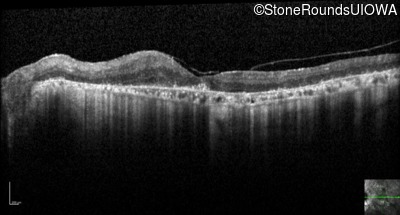

Optical Coherence Tomography - Left - 20/63 +2

Exemplar / OCT Stack